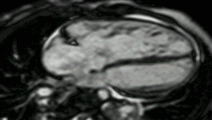

CMR in the 4 chamber view comparing the cine (left) with the late gadolinium image using inversion recovery (right). The subendocardial infarct is clearly seen. Fat around the heart also appears white.